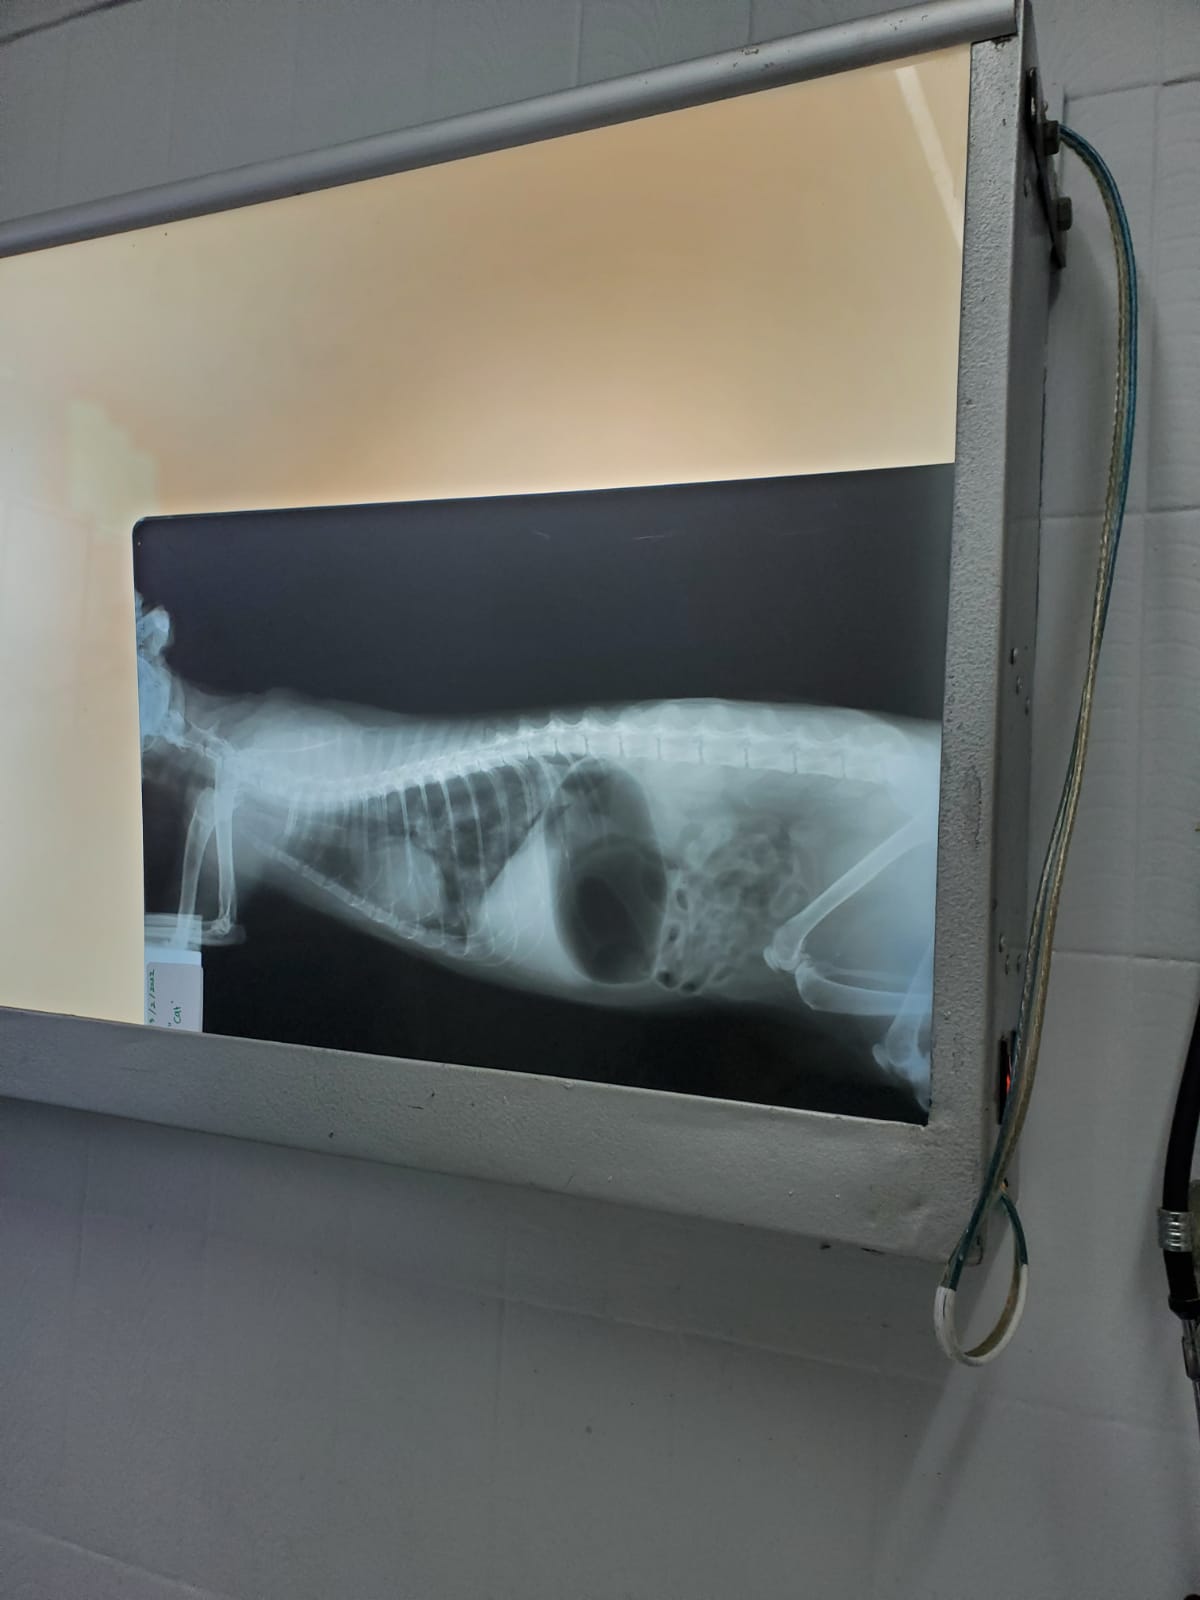

Besoknya ke vet, dan bener ada flek di paru. Trus perut udah penuh udara karena dia napas pake mulut. Maka 4 hari ini saya bolak balik bawa Aling ke dokter. Jadi pagi dia udah di klinik, untuk dirawat dengan infus dan obat. Sorenya pulang dan saya rawat di rumah.